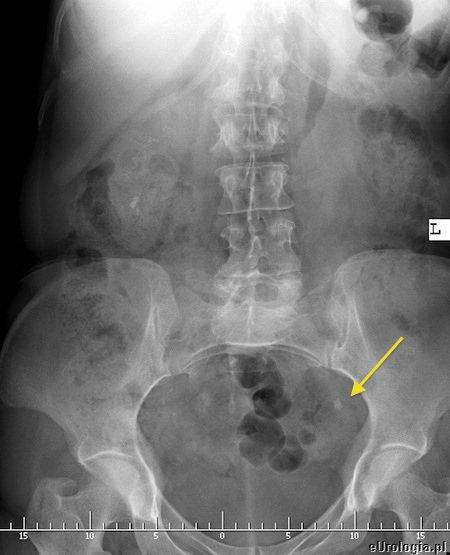

Kamica moczowodowa czyli potocznie kamień w moczowodzie jest najczęstszą przyczyną kolki nerkowej. Złogi - kamienie z nerki mogą przemieścić się do moczowodu blokując odpływ moczu z nerki. Zastój moczu w układzie kielichowo - miedniczkowym powoduje napięcie torebki nerkowej i wystąpienie ataku kolki. W zależności od lokalizacji kamień w moczowodzie może być uwidoczniony róznymi sposobami. Kamienie w górnym odcinku moczowodu i w okolicy ujścia pęcherzowego moczowodu czasami możliwe są do uwidocznienia w USG. Większość kamieni w moczowodzie widoczna jest na zdjęciu przeglądowym jamy brzusznej. W celu uwidocznienia miejsca przeszkody w odpływie moczu z nerki wykonywane jest badanie urograficzne. Urografia jest badaniem obrazowym pozwalającym na ocenę czynnościową i anatomiczną układu moczowego.

Fot. Cień uwapnionego złogu w rzucie lewego moczowodu na zdjęciu przeglądowym nerek i pęcherza.